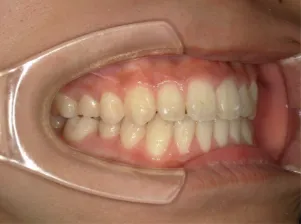

治療中④中2:マルチブラケット法へ移行:上下正中を合わせたい

*マルチブラケット法

治療後⑤中3:咬合治療終了 マルチブラケット法の期間は9か月